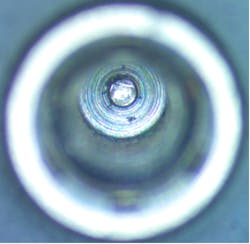

Of the seven major dental implant brands inspected, four contained visible material under magnification (57%), primarily located within the screw channel and connection (figure 1). Debris was also seen in the base of the screw channel in another brand-new implant (figure 2).